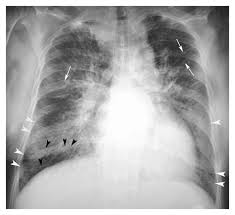

In the case of fulminant. Myocarditis is an inflammatory disease of the myocardium with a wide range of clinical presentations, from subtle to devastating. Current trends in diagnosis and treatment. Patients of suspected myocarditis are clinically evaluated to distinguish fulminant lymphocytic myocarditis from acute lymphocytic myocarditis. Myocarditis, also known as inflammatory cardiomyopathy, is inflammation of the heart muscle. • definition:myocarditis is an inflammatory disease of cardiac muscle. Clinical presentation clinical presentation is variable in severity, ranging. Journal of the american college of cardiology vol.

A position statement of the european society of cardiology working group on myocardial and pericardial diseases. In the case of fulminant. Myocarditis, also known as inflammatory cardiomyopathy, is inflammation of the heart muscle. Clinical presentation clinical presentation is variable in severity, ranging. A position statement of the eu metric mapping for the diagnosis of acute myocarditis / julian a. Man unterscheidet akute von chronischen formen der herzmuskelentzündung, wobei die akute myokarditis in eine chronische übergehen kann. Patients of suspected myocarditis are clinically evaluated to distinguish fulminant lymphocytic myocarditis from acute lymphocytic myocarditis. Myocarditis is an inflammation of the heart muscle (myocardium). Cardiomyopathies, myocarditis, and pericardial disease. Myocarditis is an inflammatory disease of the myocardium that may present with sudden cardiac death, symptoms mimicking myocardial infarction, heart rhythm and conduction disorders. Myocarditis can affect your heart muscle and your heart's electrical system, reducing your heart's ability to pump. Contemporary reviews in cardiovascular medicine. Symptoms can include shortness of breath, chest pain, decreased ability to exercise, and an irregular heartbeat.

In the case of fulminant. Journal of the american college of cardiology vol. • it can be acute, subacute, or chronic, and. More specifically, it is described as. Management, and therapy of myocarditis: Symptoms can include shortness of breath, chest pain, decreased ability to exercise, and an irregular heartbeat. 17 march 2005 suspected myocarditis in sri lanka. Myocarditis can affect your heart muscle and your heart's electrical system, reducing your heart's ability to pump.

Patients of suspected myocarditis are clinically evaluated to distinguish fulminant lymphocytic myocarditis from acute lymphocytic myocarditis. Most of the time, it is caused by an infection that reaches the heart. Cardiomyopathies, myocarditis, and pericardial disease. Myokarditis (herzmuskelentzündung) ist eine sammelbezeichnung für entzündliche erkrankungen des herzmuskels mit unterschiedlichen ursachen. Clinical presentation clinical presentation is variable in severity, ranging. Myocarditis is an inflammation of the heart muscle (myocardium). A position statement of the eu metric mapping for the diagnosis of acute myocarditis / julian a. Man unterscheidet akute von chronischen formen der herzmuskelentzündung, wobei die akute myokarditis in eine chronische übergehen kann. Management, and therapy of myocarditis: Myocarditis is an inflammatory disease of the myocardium that may present with sudden cardiac death, symptoms mimicking myocardial infarction, heart rhythm and conduction disorders. Sie kann akut oder chronisch verlaufen. In the case of fulminant. More specifically, it is described as.